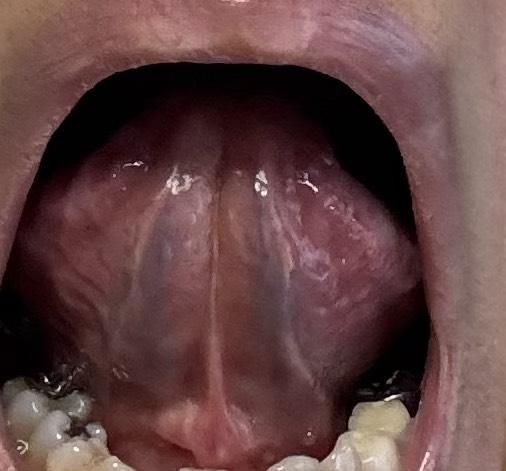

「舌の表」と「舌の裏」「両目瞼の下」4箇所のお写真見本

舌裏面